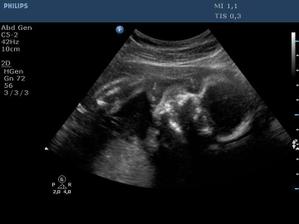

Ultrazvuk miminka - 24 týden

Z "menší protekce" u pana primáře Radiodiagnostického oddělení jsme mohli na soukromou "špionáž" naší krásné holčičky... (Pan doktor je už třetí, kdo hádá holčičku a po pravdě s tím přístrojem, co má k dispozici, bylo naprosto zřetelně vidět, že tam žádný pytlík není! :o)) Natočil nám i několik videí, kde ta naše šibalka zívala a dvakrát na nás dokonce vyplazovala jazyk. ;o)